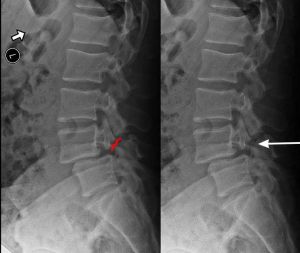

Spondylolisthesis is most commonly found in the lumbar spine as these levels bear the most weight. To assess instability, we take x-rays of a patient bending forward (flexion) and bending backwards (extension). Normally there would be no motion. The more motion seen between flexion and extension x-rays across an injured level, the greater the patient’s symptoms usually appear.

X-RAY SHOWING A PARS FRACTURE DEFECT

When we look at the spine from the side, we can imagine a scotty dog. It is outlined above. The pars fracture is seen as a collar around the dog's neck. Instability and movement can cause the neck to widen. We will see this below in an X-ray example.